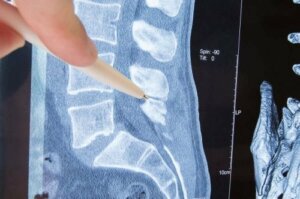

脊椎是椎骨形成的骨質結構,可以保護骨骼,讓你活動自如。脊椎兩側各有一個洞,通向身體不同部位的神經從這些洞出來。

從椎骨出來的神經成為「神經根」。神經根病變是指神經根受到壓迫。是什麼原因造成的呢?它的臨床表現是什麼?本文我們將回答這些問題,並介紹目前的治療方法。